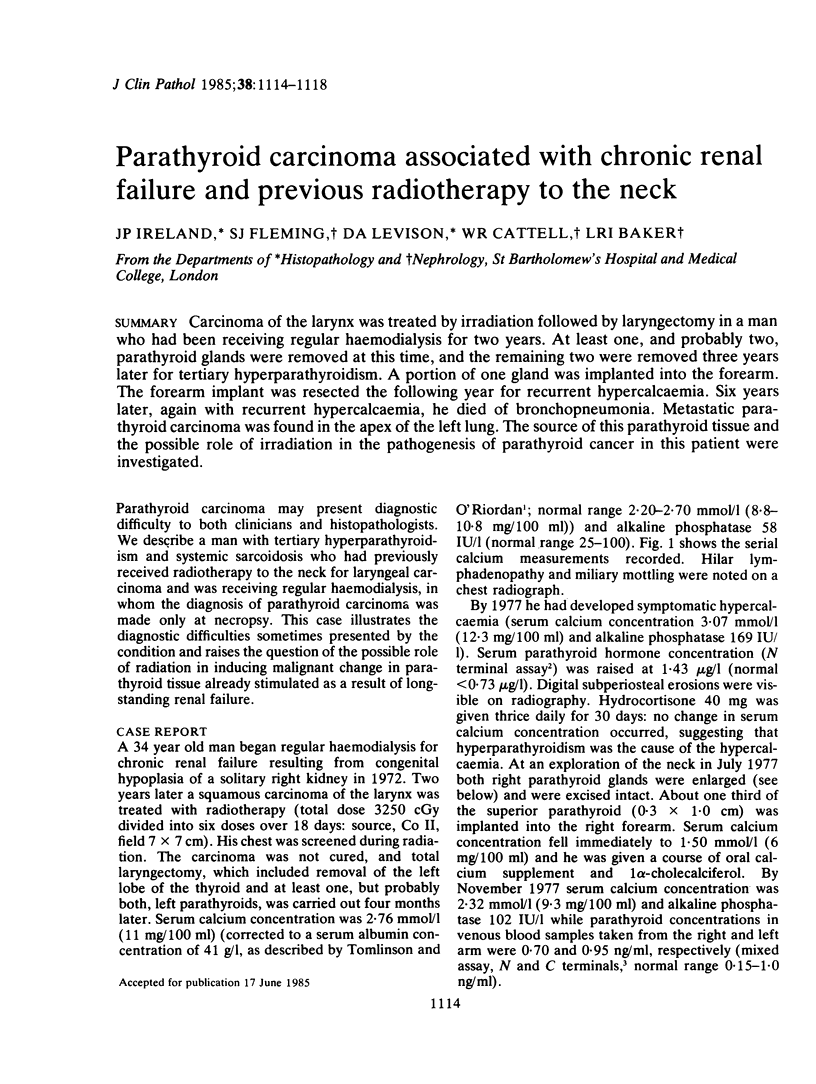

Carcinoma of the larynx was treated by irradiation followed by laryngectomy in a man who had been receiving regular haemodialysis for two years. At least one, and probably two, parathyroid glands were removed at this time, and the remaining two were removed three years later for tertiary hyperparathyroidism. A portion of one gland was implanted into the forearm. The forearm implant was resected the following year for recurrent hypercalcaemia. Six years later, again with recurrent hypercalcaemia, he died of bronchopneumonia. Metastatic parathyroid carcinoma was found in the apex of the left lung. The source of this parathyroid tissue and the possible role of irradiation in the pathogenesis of parathyroid cancer in this patient were investigated.